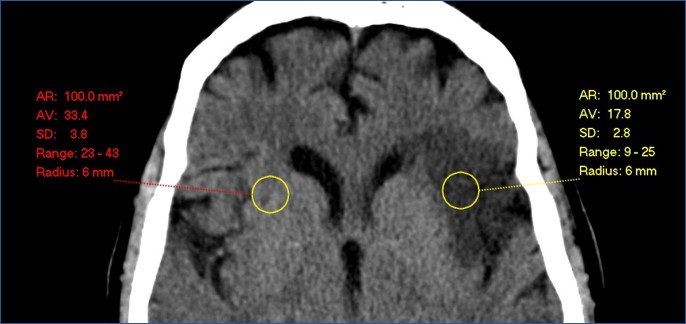

Attenuation measurements from ischaemic and normal brain are needed. These can be manually obtained with the software you already have for viewing CT: